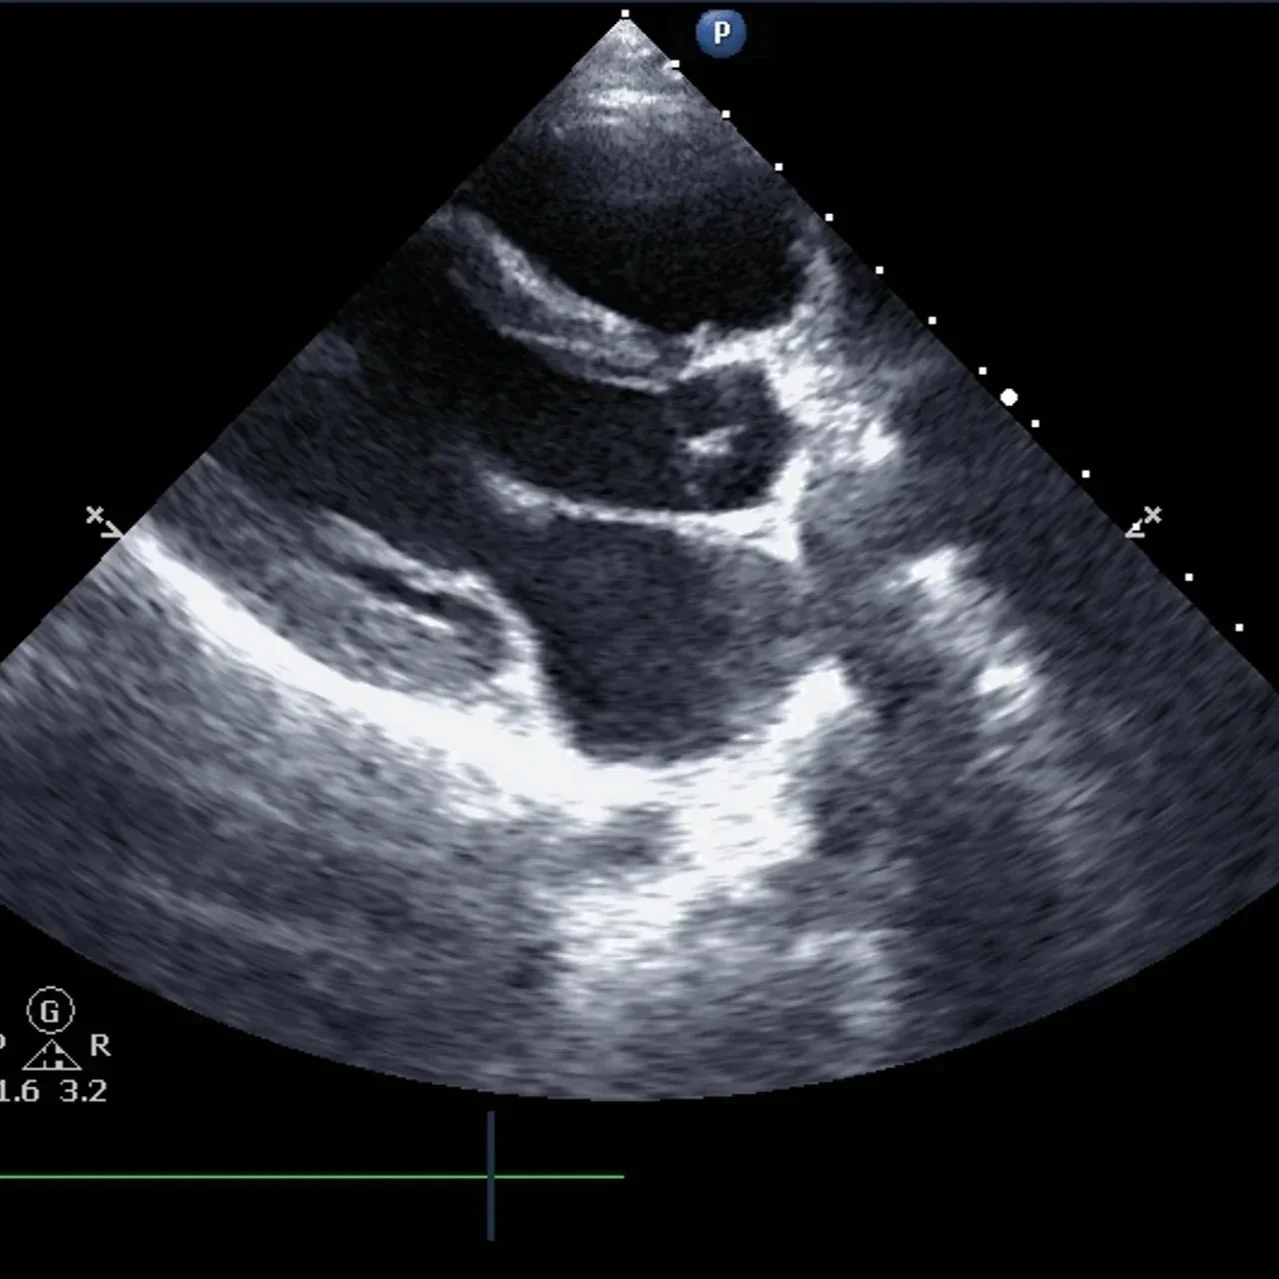

Using high-frequency sound waves, an echocardiogram provides real-time images of the heart. The procedure involves placing a transducer on the chest, sending sound waves through the body. These waves reflect back from the heart’s structures and help to produce detailed images of the heart’s valves, chambers, and blood flow.

The test is noninvasive and painless, typically finished within 30 to 60 minutes. Helping healthcare providers make informed decisions about diagnosis and treatment, it delivers a comprehensive view of the heart’s function and anatomy.